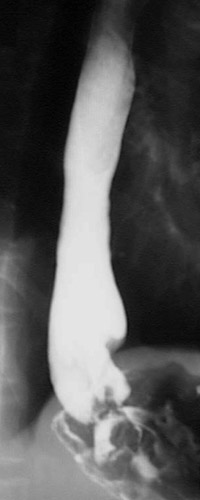

This radiograph from an upper GI series demonstrates a mass lesion distorting the lower esophagus, which proved to be a lower esophageal squamous cell carcinoma.